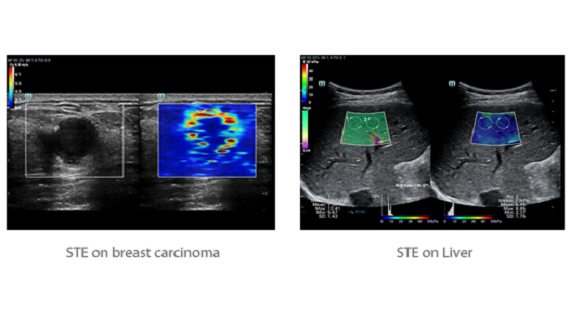

Mindray, ?irketin kuruldu?u gĂŒnden bu yana sĂŒrekli olarak tan?sal do?rulu?u iyile?tirmeye ?al??maktad?r. Devrim niteli?indeki ZONE Sonography? Teknolojisi ile desteklenen Resona 7ânin yeni ZST+ platformu, b?lge g?rĂŒntĂŒsĂŒ alma ve kanal veri i?leme ?zellikleri ile ultrason g?rĂŒntĂŒsĂŒ kalitesini daha ĂŒst bir dĂŒzeye ??kar?yor.

Resona 7, ĂŒstĂŒn dĂŒzeyde g?rĂŒntĂŒ kalitesine ek olarak, vaskĂŒler hemodinamik de?erlendirmesi i?in devrim niteli?indeki V Ak??? ile fetĂŒs CNS tan?lamas? i?in 3 boyutlu veri kĂŒmesinden dĂŒzlem g?rĂŒntĂŒsĂŒ alma konusunda en iyi birime sahip oldu?undan, klinik ara?t?rma yeterliklerini de art?rmaktad?r. En sezgisel, harekete dayal? ?oklu dokunmatik i?letim ile tĂŒm temel klinik ?zellikleri bir araya getiren Resona 7, ultrason yenili?i konusunda ger?ek anlamda yeni dalgalara ?ncĂŒlĂŒk ediyor.